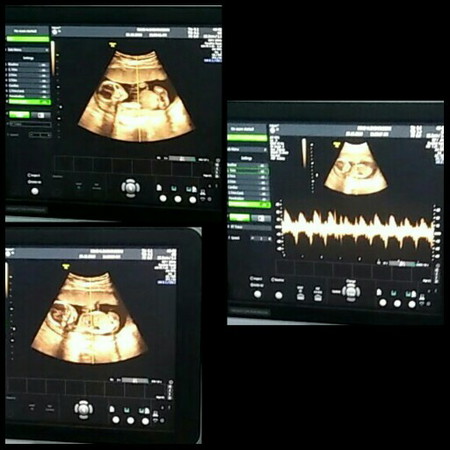

hasil USG normal

Tiada hentinya rasa syukur ini kepadamu ya Allah... Setelah kehilangan anak pertama (keguguran 3 bln) kini kau telah memberikan kembali hadiah yang sama, dan senang sekali ketika saya tau hasil USG, dokter berkata kalo si kecil sangat sehat dan normal, semuanya kata dokter bagus banget, walau pada awalnya saya masuk diruang USG badan saya gemeteran, ingin BAB dan ingin pipis sampai² si kecil pun ikut kontraksi sangking takutnya saya ada apa apa pada kehamilan saya ataupun si kecil, karna saya mengalami keguguran tanpa kuret,,, tapi suami saya terus menenangkan saya dan memberikan suport serta senyuman kepada saya, dan disitulah saya kembali bersemangat dan saya yakin kalo tidak ada masalah apa apa pada kandungan saya ataupun dengan si kecil,,, alhamdulillah... Hasilnya sangat mengejutkan ketika dokter memberi tahu detak jantung si kecil sangat bagus, air ketuban bersih, placenta normal, dan intinya baby sehat banget walaupun jenis kelamin belum terlihat karna usia baru 4 bln,, hemm... Disitu saya sangat senang dan kembali tersenyum seperti tidak menyangka akan mukjizat allah, suami saya pun sampai bengong ketika disuruh merekam sama dokter sangking perasaan senang, bahagia dan campur aduk pokoknya....... Bagi bunda² semuanya jaga baik² ya kandungannya jangan capek², dan ingat bahwa Allah itu sayang sama kita sehingga kita masih diberi kepercayaan untuk menjadi seorang ibu ????